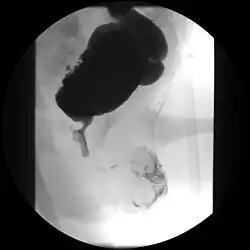

Ultrasound imaging can give information on the shape of the bladder, post-void residual volume, and evidence of kidney damage such as kidney size, thickness or ureteral dilation.[12] Trabeculated bladder on ultrasound indicates high risk of developing urinary tract abnormalities such as hydronephrosis and stones.[13] A voiding cystourethrography study uses contrast dye to obtain images of the bladder both when it is full and after urination which can show changes in bladder shape consistent with neurogenic bladder.[12]